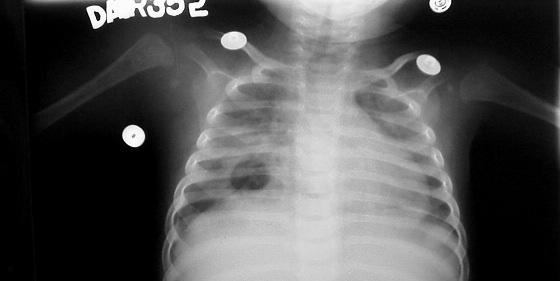

Infant presenting after 6 weeks of symptoms, with swelling over the arm & shoulder right and reluctance to move the limb due to pain. Was on different antibiotics since then.

2. X-ray in the 1st week of symptoms did not show any changes of right humerus.